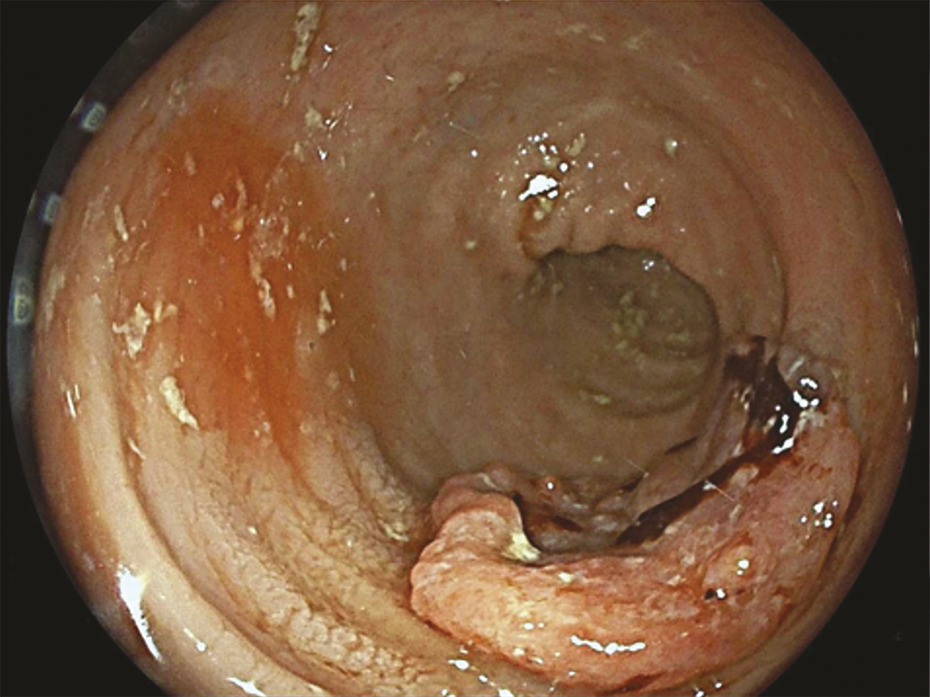

La coloscopie, sous anesthésie générale, est l’examen de première intention dans la plupart des cas de rectorragies. Si elle met en évidence une tumeur rectale, elle peut être complétée immédiatement ou dans un second temps par une rectoscopie rigide, permettant d’évaluer plus précisément la distance entre le pôle inférieur de la tumeur et la marge anale (mesure la plus reproductible) et/ou le pôle supérieur du sphincter. L’examen endoscopique permet également de décrire la lésion rectale (taille, aspect macroscopique, circonférence d’implantation) et de recueillir de multiples biopsies, indispensables au diagnostic (fig. 1 et 2 ).

– la présence ou non d’arguments en faveur d’une histologie mucineuse, de plus mauvais pronostic (tumeur en hypersignal T2)4 [fig. 4 ] ;

– la présence ou non d’arguments en faveur d’une histologie mucineuse, de plus mauvais pronostic (tumeur en hypersignal T2)4 [